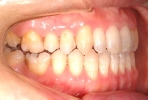

| マルチブラケット終了時

| 治療後3年経過時